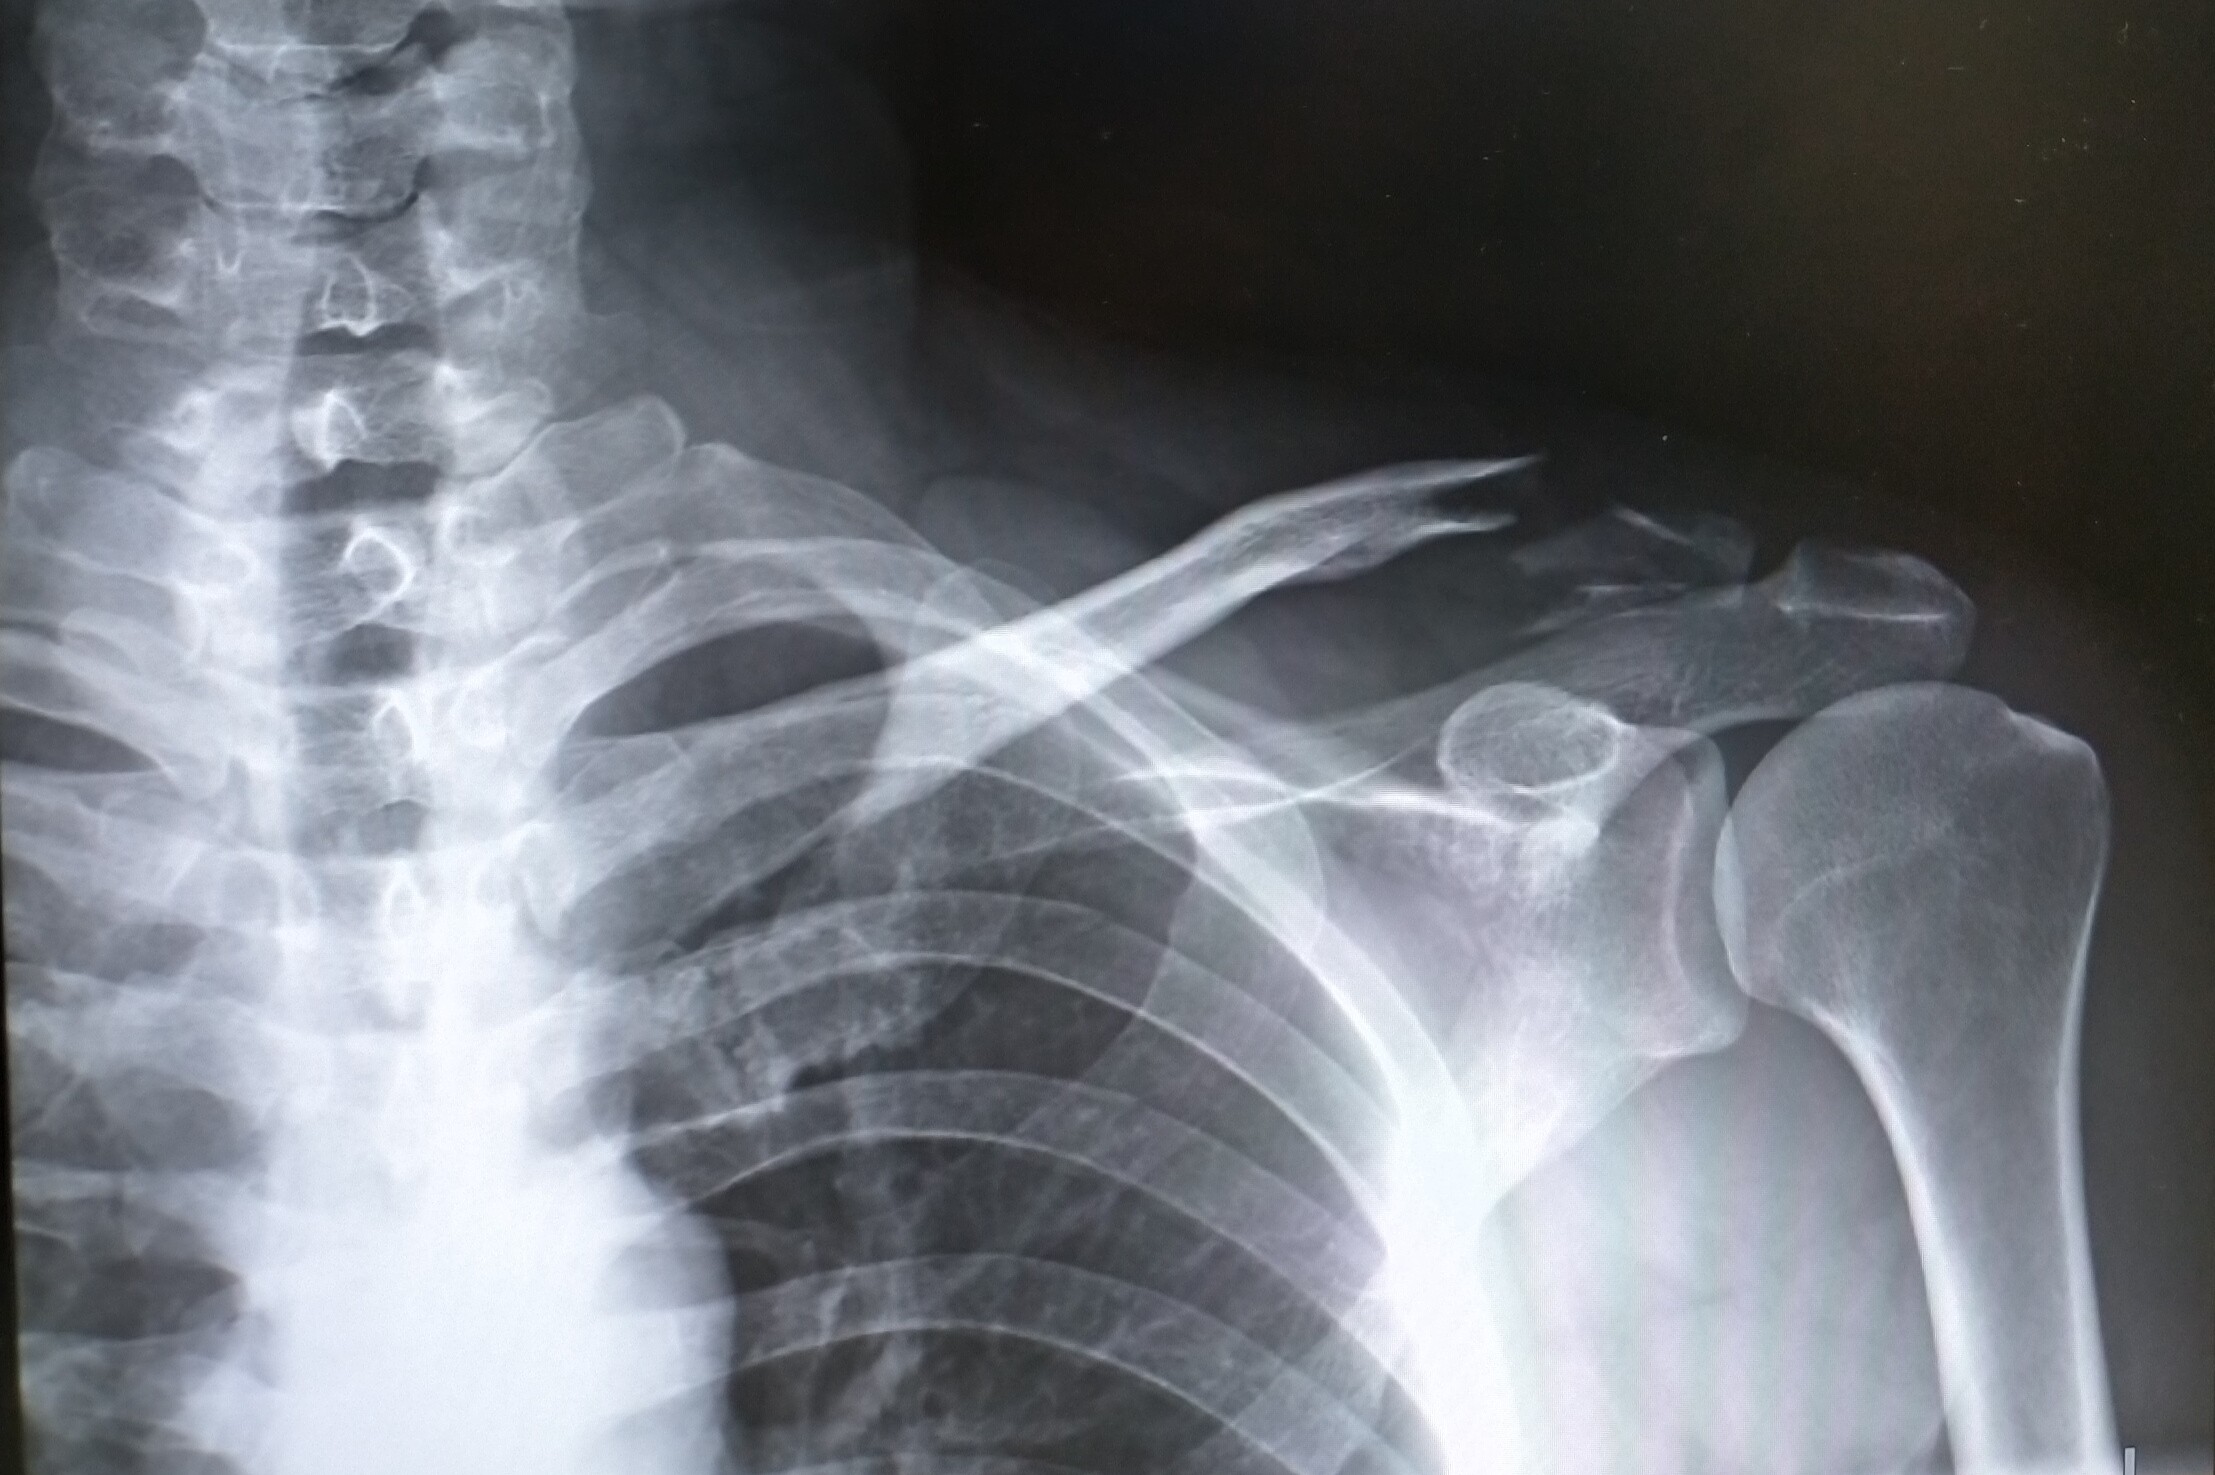

スタンダード骨折手術治療 上肢 単行本 – 22/4/1 インプラント (プレート, スクリュー, 髄内釘など), アプローチ法 (前方, 後方など), 骨折の状態 (関節内骨折, 関節外骨折, 単純骨折, 粉砕骨折)など, 現 年間300例の骨折の手術の執刀をしています 骨折の正しい知識をブログで発信しています /stmybox 鎖骨骨折はバイク事故やレジャーで肩を下にして転倒することで受傷すること

鎖骨骨折の痛みは だいたい一か月ほど 続きます。 はじめはものすごく痛いのですが、安静にしていれば徐々に痛みは引いていきます。 鎖骨という部位は手や足のように、がちがちに